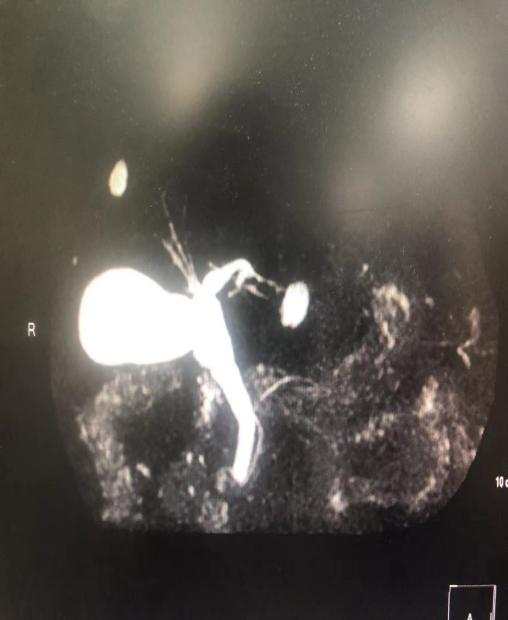

胆道子母镜图:左右肝管分叉处

胆道子母镜图:胆囊管开口处